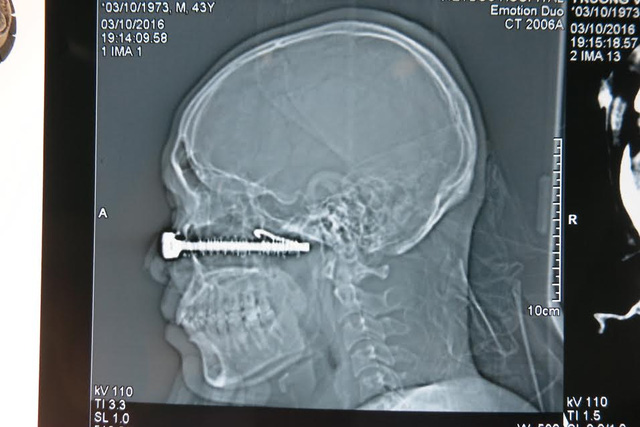

VBF-Mới đây tập thể y bác sĩ VN đã mổ cấp cứu thành công 1 bệnh nhân đang trong tình trạng nguy kịch tại bệnh viện Việt Đức. Theo đó nạn nhân đã bị 1 đinh sắt dài 10cm đâm thẳng vào vùng mắt sau khi bị ngã xe. Ca mổ đã diễn ra xuyên đêm và thành công tốt đẹp.Tai nạn trong chớp mắt đã khiến một chiếc đinh vít (kèm móc sắt) dài tới hơn10 cm găm xuyên qua mặt một người đàn ông sát ngay dưới một bên mắt. Một cuộc hội chẩn liên viện giữa bệnh viện (BV) Việt Đức và BV Mắt Trung ương nhanh chóng diễn ra tại BV Việt Đức sau khi tiếp nhận bệnh nhân.

Một ca mổ cấp cứu trong đêm có đầy đủ các chuyên khoa: Phẫu thuật tạo hình hàm mặt, Thần kinh, Mạch máu, Mắt, Gây mê hồi sức... tiến hành lấy bỏ chiếc đinh vít khủng khiếp đâm sâu gần 10 cm ra khỏi khuôn mặt bệnh nhân.

Nhìn lại dị vật đã găm sâu vào mặt bệnh nhân Trương Văn T. 43 tuổi (Tuyên Quang) lúc đó chúng tôi không khỏi rùng mình. Đó là một chiếc đinh vít cỡ cực đại có các vòng lò xo xoắn xung quanh thân kèm móc sắt uốn cong như lưỡi câu ở phía đầu.

TS. BS. Nguyễn Hồng Hà, Trưởng khoa Phẫu thuật tạo hình hàm mặt BV Việt Đức cho biết:"Nhìn phim chụp từ BV tỉnh cho thấy tổn thương rất phức tạp, nên khi tiếp nhận các bác sĩ khẩn trương đặt các đường ven truyền, hồi sức, giảm đau cho BN và chụp lại phimcắt lớp. Trên phim CT cho thấy vị trí của đầu đinh vít gần chạm vào nền sọ (chưa xuyên vào trong não) và các mạch máu lớn.Tuy nhiên đứng trước ca mổ như vậy, các bác sĩ phải hội chẩn chuẩn bị hết sức kỹ càng, các biện pháp dự phòng tối ưu nhất được đề ra".Cuộc hội chẩn liên viện, liên khoa: phẫu thuật tạo hình,mắt (bác sĩ bệnh viện Mắt Trung ương), mạch máu (dự phòng khâu nối mạch máu rách), thần kinh (dự phòng trường hợp có huyết khối trong mạch cảnh phải mở hộp sọ để xử trí), gây mê hồi sức diễn ra lúc 22h ngày 3/10/2016 tại BV Việt Đức.

22h30 phút, ThS. BS. Vũ Trung Trực, khoa Phẫu Thuật tạo hình - hàm mặt phối hợp cùng kíp phẫu thuật, gây mê hồi sức kiểm soát huyết áp của bệnh nhân (để giảm nguy cơ mất máu trong trường hợp có tổn thương mạch), sau đó tiến hành mở rộng vết thương. Đinh đâm xuyên từ thành trước đến thành sau của xoang hàm, vào hố chân bướm hàm (giữa xương bướm và xoang hàm phía sau) là vùng liên quan đến các tổ chức thần kinh, mạch máu từ tim lên não và từ trên não xuống; gần chạm vào động mạch cảnh (là động mạch rất lớn đi từ tim xuyên qua vùng chân bướm hàm lên nuôi não), cách động mạch cảnh 5 mm (rất may chưa tổn thương đến mạch cảnh).

Đinh đâm sâu toàn bộ xương mặt, đến tận nền sọ, móc câu sắt trên đinh ngoắc vào sâu trong xương mặt cùng với lò xo xung quanh nên rất khó rút ra.Vỡ toàn bộ sàn ổ mắt, vỡ xương thành trước hốc mắt và tổn thương cực dưới của nhãn cầu.